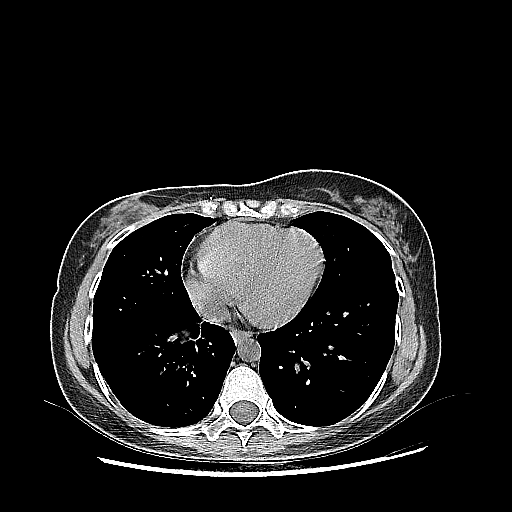

Generated VENOUS CT scan (A→B translation)

Full window (WL 1023.5, WW 4095 β†’ Low βˆ’1024, High +3071)

Actual HU range: [-1024.0, 892.4]